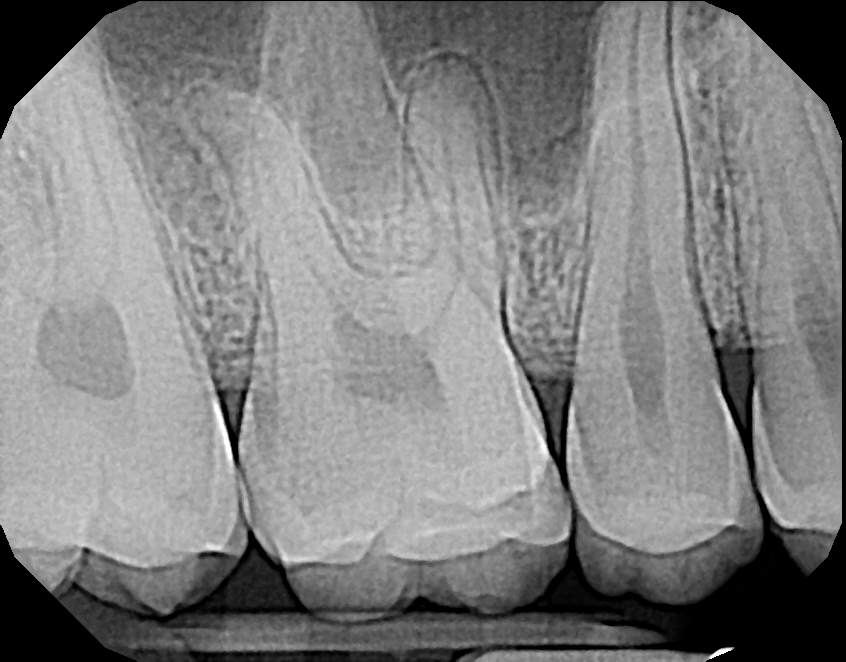

Image Quality

Ultimately, quality is the most important factor in a dental X-ray sensor. A sharp image ensures a proper diagnosis for patients. The Dream Sensor produces easy-to-view, crisp images that work with almost any existing dental software. The results of the direct comparison of DentiMax vs. Dexis are clear.

X-ray taken with the DentiMax sensor shown in Sidexis 4™ software |

![]() X-ray taken with the Dexis™ sensor |